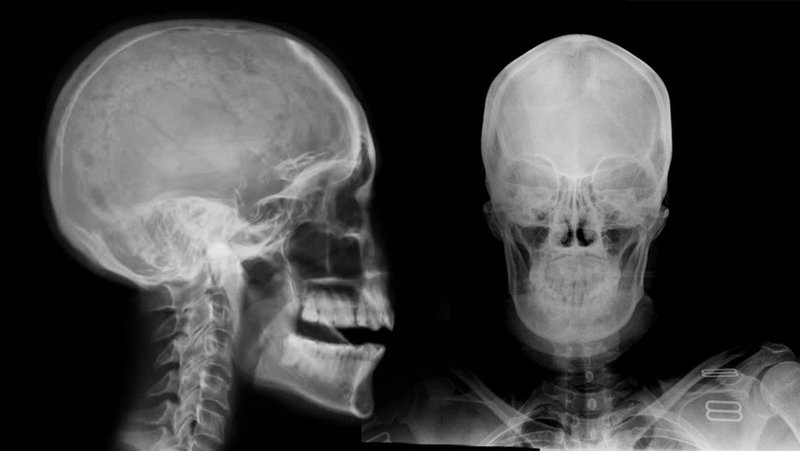

Ngoài việc thăm khám thông thường, chụp phim sọ não còn có vai trò trong chẩn đoán hội chứng tiền đình, đặc biệt là phát hiện các nguyên nhân của hội chứng tiền đình trung ương. Các phương tiện thường được chỉ định là chụp cộng hưởng từ (MRI), chụp cắt lớp vi tính (CT).